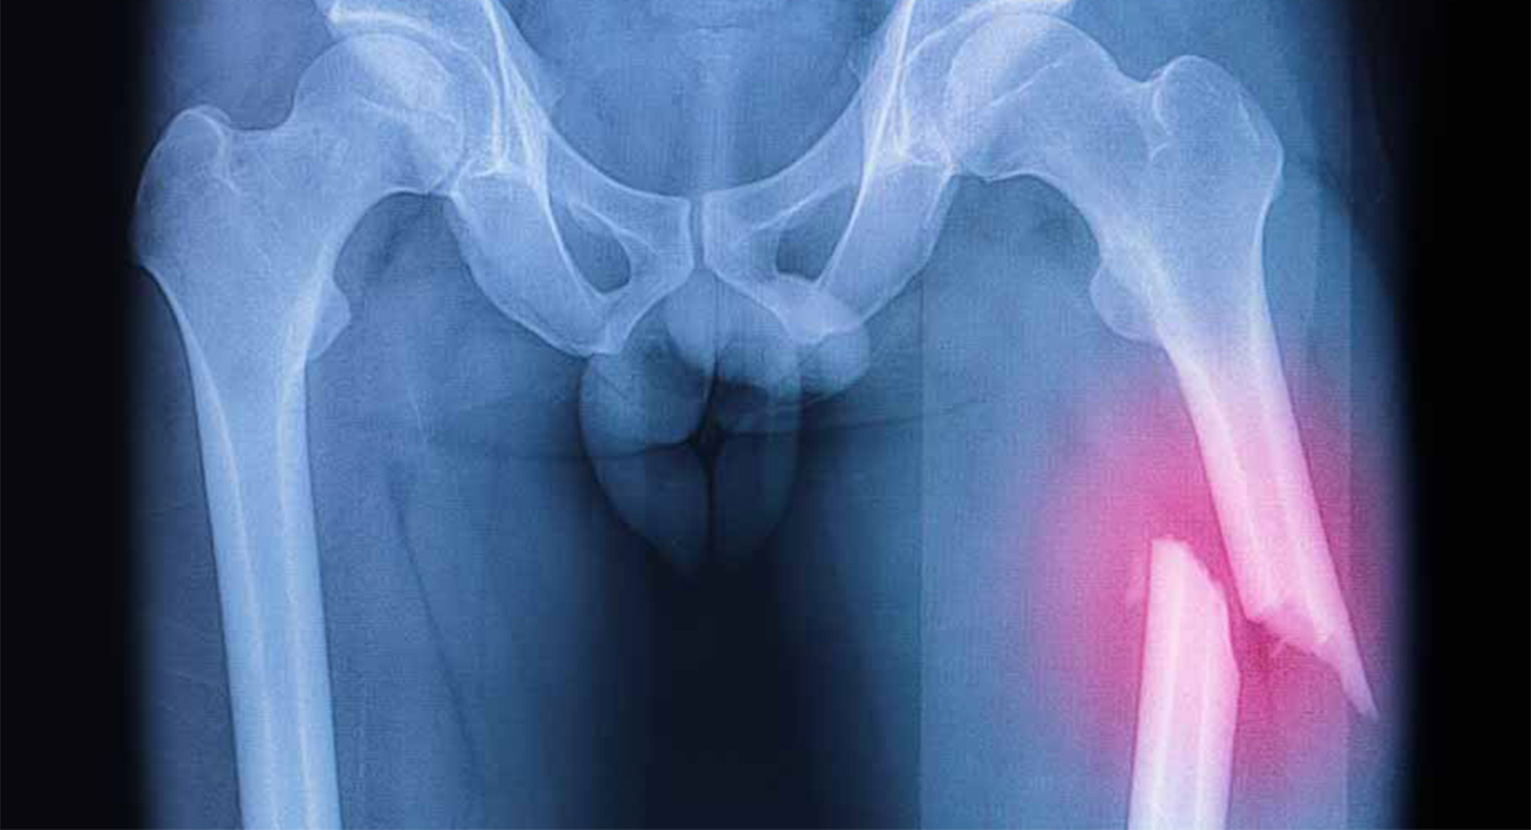

I tipi di frattura sono molteplici, in quanto si tratta di un osso molto lungo e anatomicamente complesso. Per semplicità possiamo classificare le fratture in 4 diverse tipologie. La prima è la frattura della diafisi: quando è coinvolta la parte lunga del femore (nell’apertura in un’immagine Inran, ndr). Poi c’è la frattura sottocapitata: quando si localizza subito al di sotto della testa del femore. La terza è la frattura del collo: quando si localizza in un punto del collo del femore. Quindi la frattura trocanterica: quando coinvolge uno o entrambi i trocanteri (le sporgenze, grande e piccola, nella parte superiore del femore, ndr).

Purtroppo in caso di frattura esposta, quindi quando la struttura ossea lacera i tessuti, possono verificarsi lesioni a livello dei muscoli adiacenti all’osso interessato. Un caso eclatante è quello avvenuto recentemente a Chris Froome, che a causa di un grave incidente ha riportato, oltre ad altre fratture e contusioni, la frattura esposta del femore destro con perdite ematiche ingenti. A causa di questo grave incidente la carriera del corridore inglese è parsa fortemente a rischio, ma la sua forza di volontà e il suo ottimo recupero fisico gli hanno permesso di rientrare all’attività agonistica. Seppure al momento senza riuscire a tornare ai livelli precedenti.